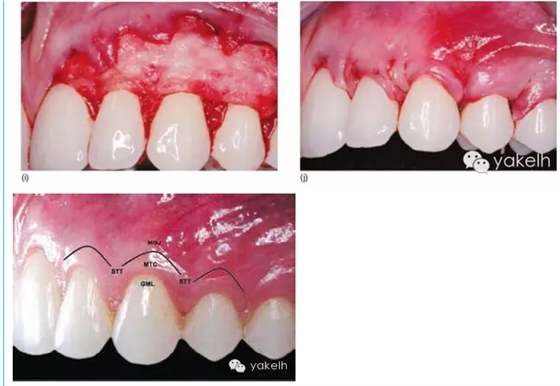

¤¤若使用脫細胞真皮基質(zhì),組織瓣瓣的剝離方法與前述相同。在口外用#15刀片將干燥的脫細胞真皮基質(zhì)移植物切割成所需大小,然后在生理鹽水溶液中浸泡15分鐘潤濕移植物。之后將潤濕后柔軟的膜進行精確塑形調(diào)整,充分貼合術區(qū)、完全覆蓋缺損。將移植物放置于釉牙骨質(zhì)界,其上緣及側緣越過缺損區(qū)牙槽嵴根方缺損至少0.7~1.0mm。放置時,脫細胞真皮基質(zhì)的基底面(帶小凹陷的表面)貼合骨組織和根面,而結締組織或真皮層面則貼合組織瓣(圖5.14a~k)。

圖5.14 (a)使用Emdogain®和AlloDerm®治療Ⅰ/Ⅱ類牙齦退縮。(b,c)頰側牙齦退縮深度,在鄰牙牙齦乳頭做標記,從尖端到基底。(d)分離全厚瓣和半厚瓣,以增加組織瓣的的活動度。(e)用細金剛砂車針進行根面平整,減少根面凸度,注意平整時勿加壓。(f)用金剛砂球鉆去除齦乳頭上皮。(g)將AlloDerm®浸泡于生理鹽水中潤濕后取出,基底面與血液接觸不吸收血液。(h)真皮面可吸收血液,真皮面應貼合組織瓣。(i)AlloDerm®膜覆蓋于齦退縮根面上。(j)AlloDerm®底部注入Emdogain®凝膠,然后將組織瓣冠向復位,縫合固定。(k)術后1年所有牙齦退縮位點根面完全被牙齦覆蓋,獲得滿意的紅色美學效果。GML,齦緣水平;MTC,邊緣組織輪廓;STT,軟組織質(zhì)地;MGJ,膜齦聯(lián)合。

¤¤使用4-0的縫線和縫針進行牽引,將脫細胞真皮基質(zhì)從遠中插入每個齦乳頭下面的隧道,在隧道內(nèi)向根方和側方推進(圖5.15a~i)。使用冠向復位瓣覆蓋穩(wěn)定脫細胞基質(zhì),以相同的5-0 VicrylTM丙交醋雙聚合物910縫線做懸吊縫合。需要強調(diào)的是:表面組織瓣必須完全覆蓋膜塊,以防材料冠方部分暴露和細菌繁殖,從而減少并發(fā)癥。之后,將釉基質(zhì)衍生物凝膠注入組織瓣下方脫細胞真皮基質(zhì)底部,覆蓋處理后的根面(Saadoun,2008)。多余的凝膠覆蓋在瓣的外表面,外層以術后用含氯己定的敷料保護。

圖5.15 (a)患者牙齒著色,全口牙齦退縮。(b)使用齦乳頭剝離器翻開齦乳頭基底,保留齦乳頭尖端仍附著于骨面,如圖所示為器械放置。(c)器械進入前。(d)頰側深半厚瓣隧道。(e)準備縫針、縫線,穿過AlloDerm®,再將縫針穿過齦乳頭底部。(f)以縫針牽引AlloDerm®穿過齦乳頭底部。(g)調(diào)整AlloDerm®位于隧道瓣下方的位置,縫合固定。(h)以懸吊縫合冠向復位組織瓣,底部注入凝膠。(i)1年后可見牙齦退縮位點重新獲得牙齦覆蓋。